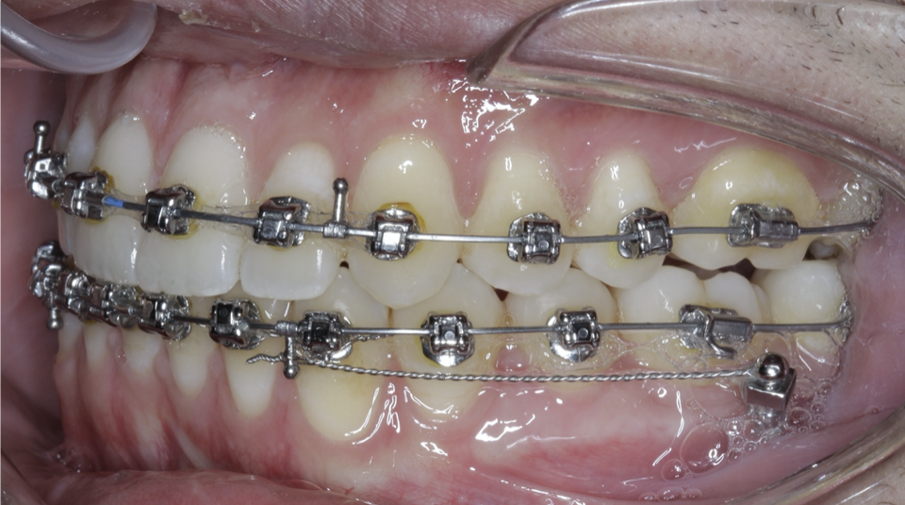

A great solution for Class III patients in need of mandibular distalisation for profile aesthetics and dental function is buccal shelf TADs. This solution allows for noncompliance correction of Class III cases with decreased compensation of the maxillary arch (Figs. 42–45, beginning of treatment). For these cases, a 2 × 12 mm Ortho Bone Screw is placed mesial to teeth #47 and #37 into the buccal shelf of the mandibular body. If the patient has mandibular third molars, then they are extracted right before the TADs are placed once in the stainless-steel wires.

Once the patient has progressed to stainless-steel wires, buccal shelf TADs are placed. A mandibular pre-posted stainless-steel wire is used, and a VectorTAS NiTi closing spring is placed from the buccal shelf TAD to the post (Fig. 46). Once the Class III has been corrected, a steel ligature is used to retain the Class III malocclusion while finishing and detailing are completed (Figs. 47–51, end of treatment).